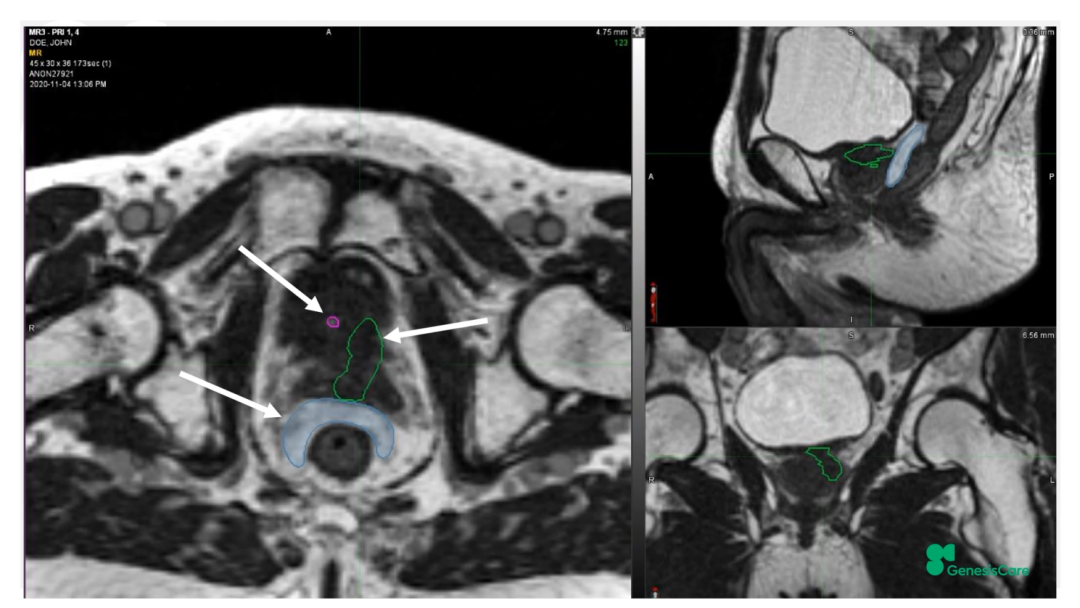

Dr. Camilleri介绍了一位72岁,在2006年接受了55Gy/20F放疗后复发的前列腺癌患者。当时它的PSA为28,局部晚期,期别为T3aN0M0。PET-CT显示前列腺左后部局部高代谢,活检也证实了这一点,并且活检结果表明肿瘤侵入左侧精囊腺底部。将其MRIdian MRI图像和PET-CT图像融合后,再根据活检结果确定靶区,见Figure 20-22,并制作放疗计划。放疗剂量为35Gy/5次,凝胶阻隔物很好地包含了直肠,见Figure 23,靶区和危及器官受量见Figure 24。患者于2020年12月接受治疗,他体质很好,在放疗期间和之后,坚持每周三次5公里跑步,始终未出现GU和GI毒性。他的PSA最低值为0.45,在2022年5月的随访数据中,睾丸激素水平回到了正常的33%。在2022年1月的放疗后PSMA PET的图像上,未见肿瘤高代谢见Figure 25。

Figure 23 放疗后复发的前列腺癌患者在MRIdian上的放疗计划

Figure 24 放疗后复发的前列腺癌患者放疗计划中靶区和危及器官的受量